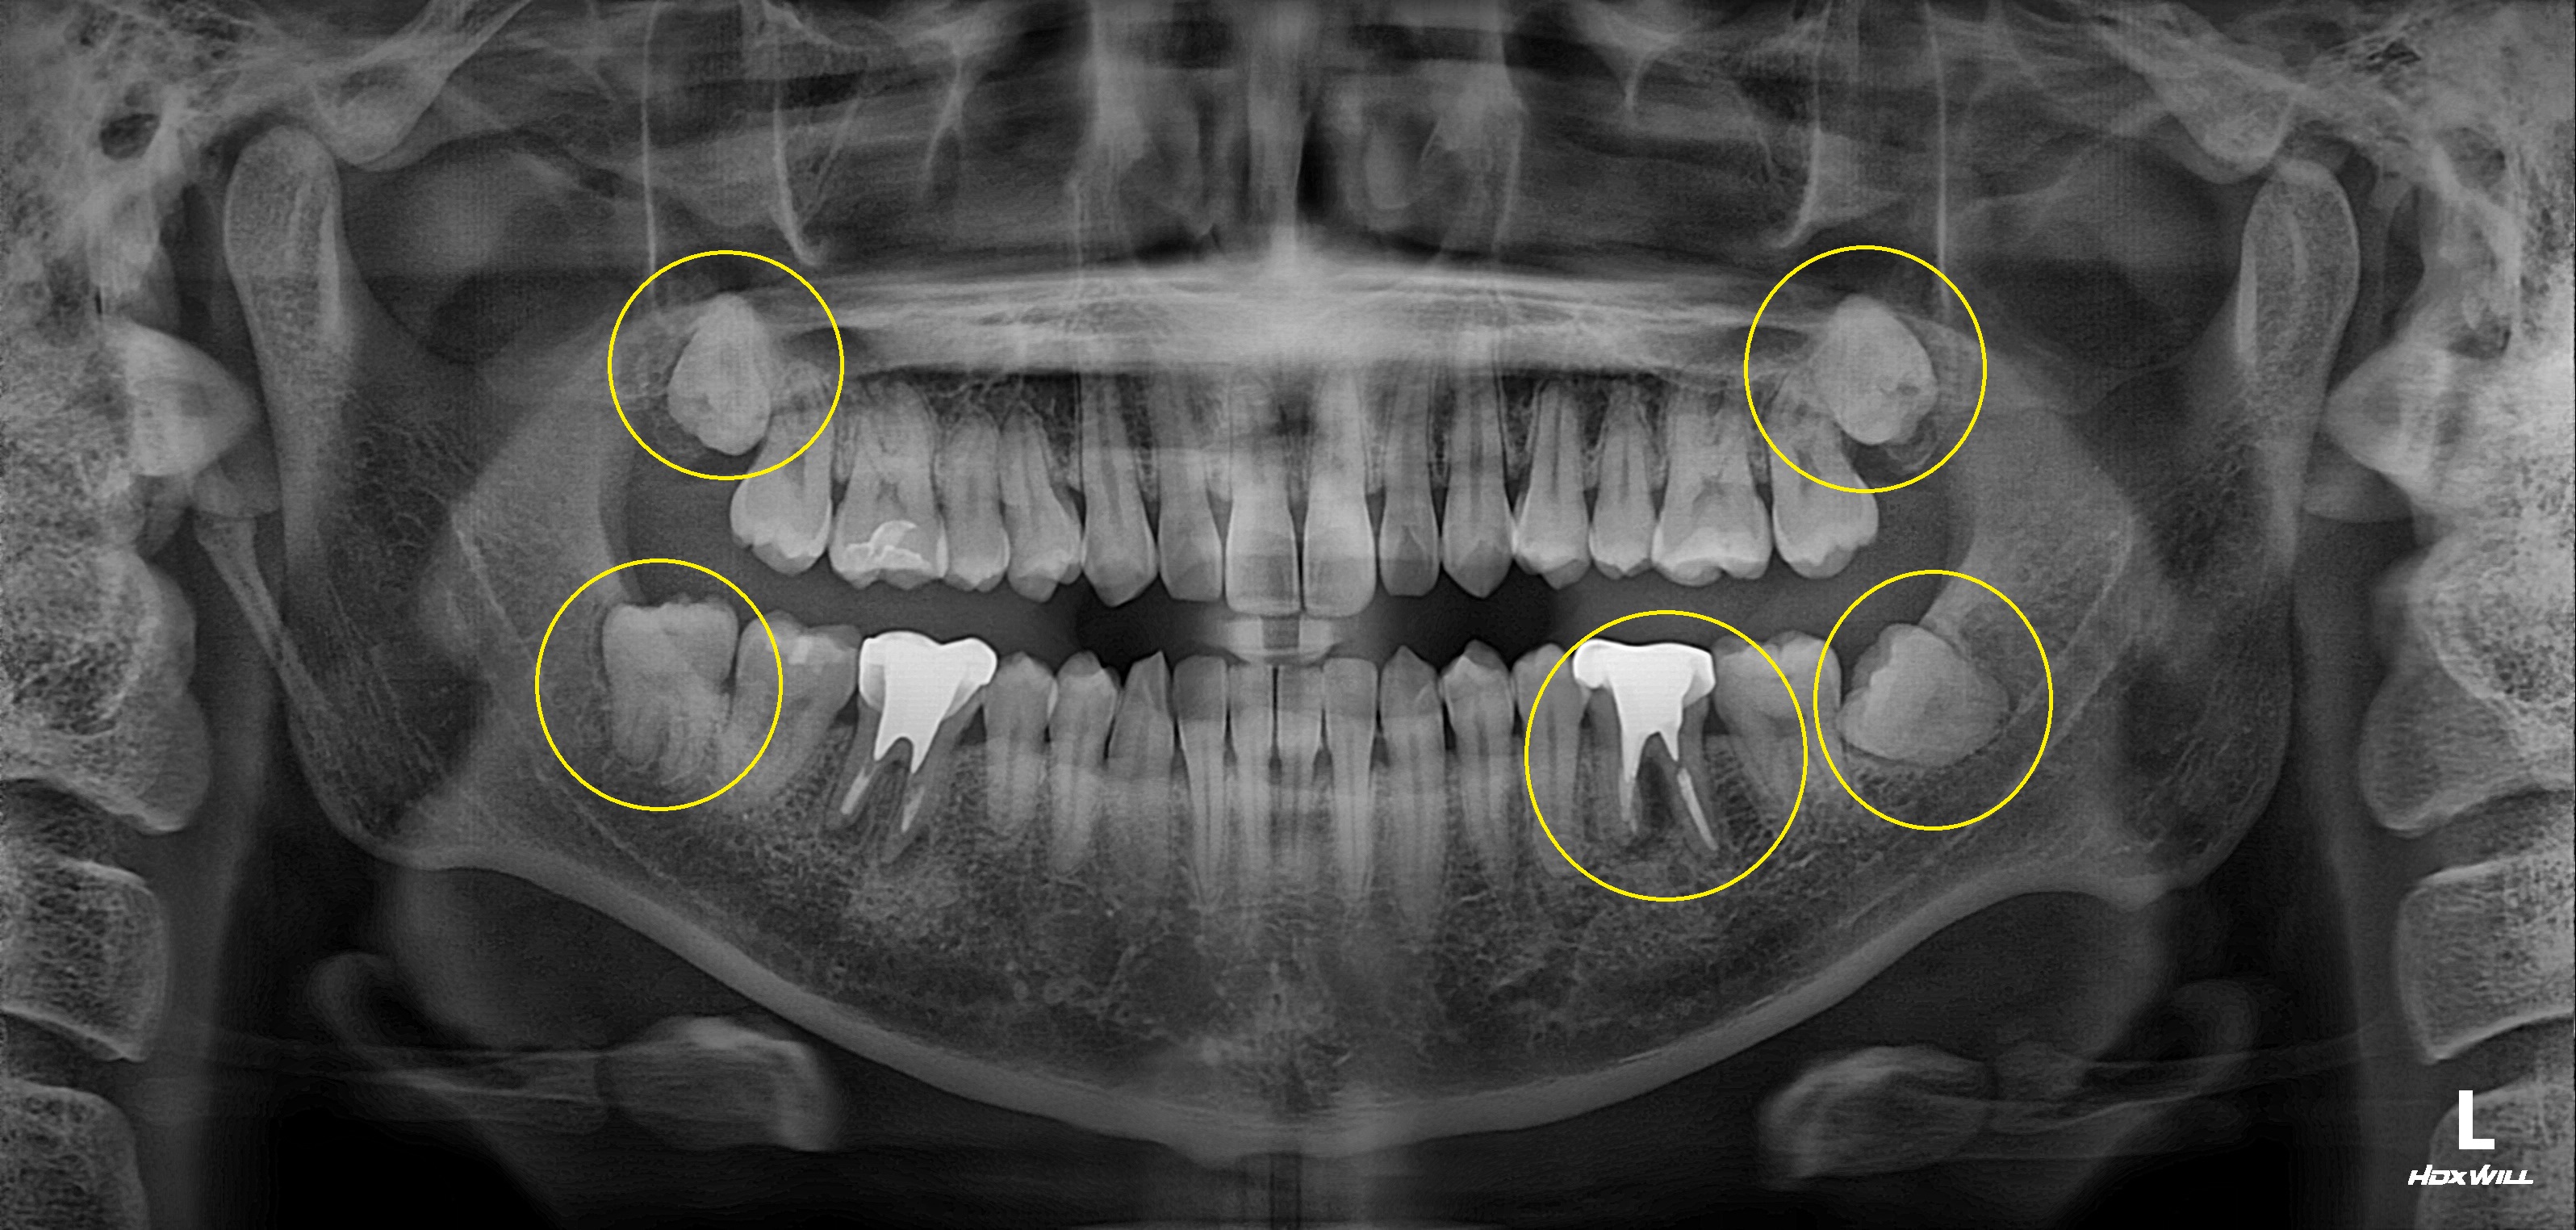

완전매복치사랑니 발치 + 구치부 임플란트 사례

전후사진

수술 전

수술 후